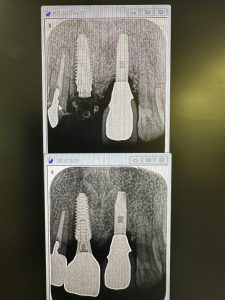

次は久しぶりの定期検診

不良肉芽が凄かった方

プラットフォームスイッチングのお陰

皮質骨がシャープになっている 安定